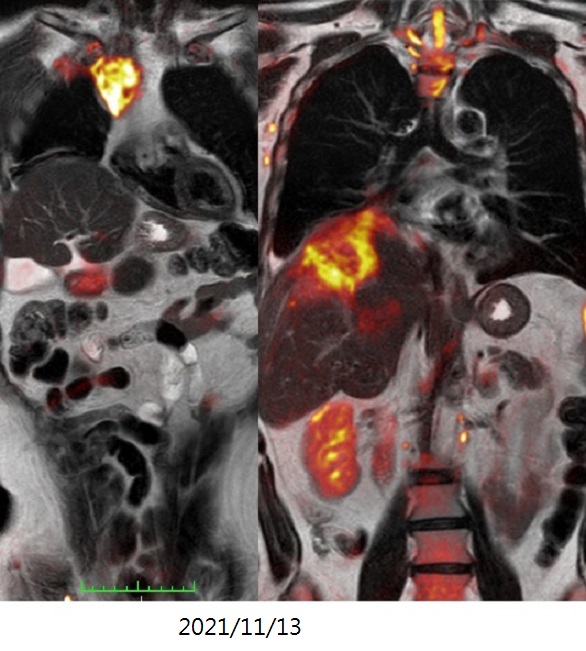

血管內光動脈灌注治療之基因檢查圖像的變化(升結腸癌、多處肺、肝、淋巴結轉移)